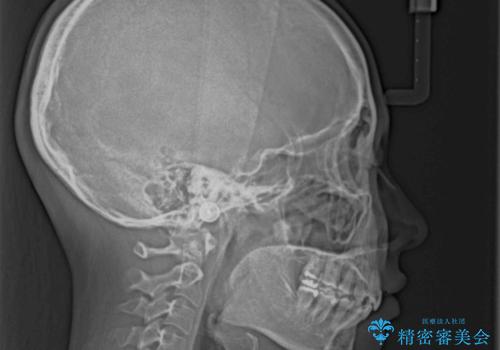

下顎骨の左右差や、上顎骨の前方位などが認められたため、上下左右の第1小臼歯4本を抜歯し、ワイヤー装置にて矯正治療を行うこととしました。

骨格的な左右差がありましたが、何とか当初予定していた期間で、左右対称の咬み合わせに仕上げることができました。